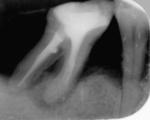

Po 30 zabiegach magnetostymulacji zdjęcie RTG wykazało zagęszczanie się struktury kostnej w miejscu osteolizy okołowierzchołkowej oraz brzegu wyrostka zębodołowego (ryc. 2).

Po 45 zabiegach widoczna jest regeneracja struktury kostnej przy obu korzeniach, zmineralizowany brzeg wyrostka zębodołowego (ryc. 3).

Brzeg wyrostka nie uległ regeneracji (odbudowie do granic fizjologicznych), lecz wyraźnie zagęściła się struktura kostna. Nastąpiło zagęszczenie beleczek kostnych w okolicy międzykorzeniowej oraz regeneracja perforacji korzenia dalszego. Badania Dojs wskazały ponadto bardzo ciekawe zjawisko zagęszczania się struktury kości zdrowej (badania w systemie Digora).[7] Korzenie bliższe zęba nie zostały udrożnione ze względu na ich obliterację. Ponadto ząb wykazywał zbyt dużą ruchomość, aby przeprowadzić leczenie prawidłowo. Korzenie wypełniono gutaperką z uszczelniaczem AH Plus. Pacjentka była pod kontrolą przez pięć lat. W tym czasie nie stwierdzono żadnych powikłań. Zdjęcia RTG wykonano techniką kąta prostego w systemie Digora. Zdjęcia wykonane przez dr n. med. A. Dojs prezentują zagęszczanie się struktury kostnej po kolejnych zabiegach.